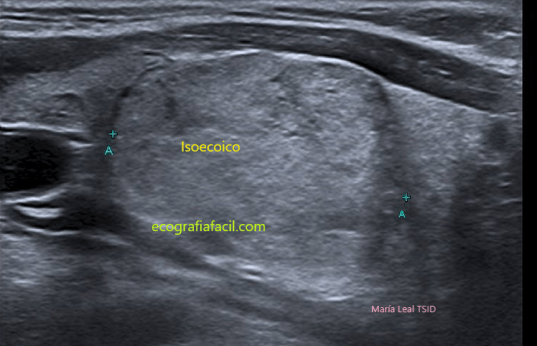

HIPERECOICO/ISOECOICO:

Para definir la ecogenicidad de los nódulos isoecoicos se compara con el parénquima de la glándula tiroidea y para nódulos hipoecoico, hiperecoico o muy hiperecoico conviene compararla con la del músculo adyacente (músculo esternocleidomastoideo).

TI-RADS 2

Sin sospecha de malignidad

COMPOSICIÓN: SólidoQuística             1

ECOGENICIDAD: Isoecoica-Anecoica     1

FORMA: Más ancho que largo                0

MARGEN: Liso                                            0

FOCOS ECOGENICOS: Coloide                 0

2 puntos